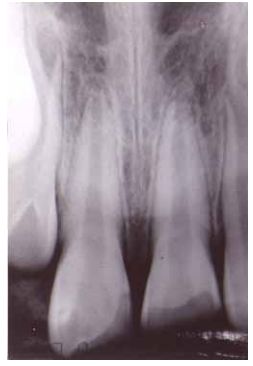

43. 9 歲男孩因當天外傷門牙斷裂求診,其 X 光如圖,對左上正中門牙齒髓而言,下列何者為最佳處置? (A)根管治療 (B)根尖成形術(apexification) (C)直接覆髓術(direct pulp capping) (D)部分冠髓切除術(partial pulpotomy)